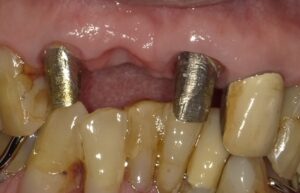

しかしブリッジを入れるためには両隣の歯を削らないといけません。

しかし画像のようにたくさん歯を削ると冷たいものや熱いものに

しみてきて神経を取らないといけない可能性が出てきます。

神経を取ると歯が割れる可能性も出てきます。